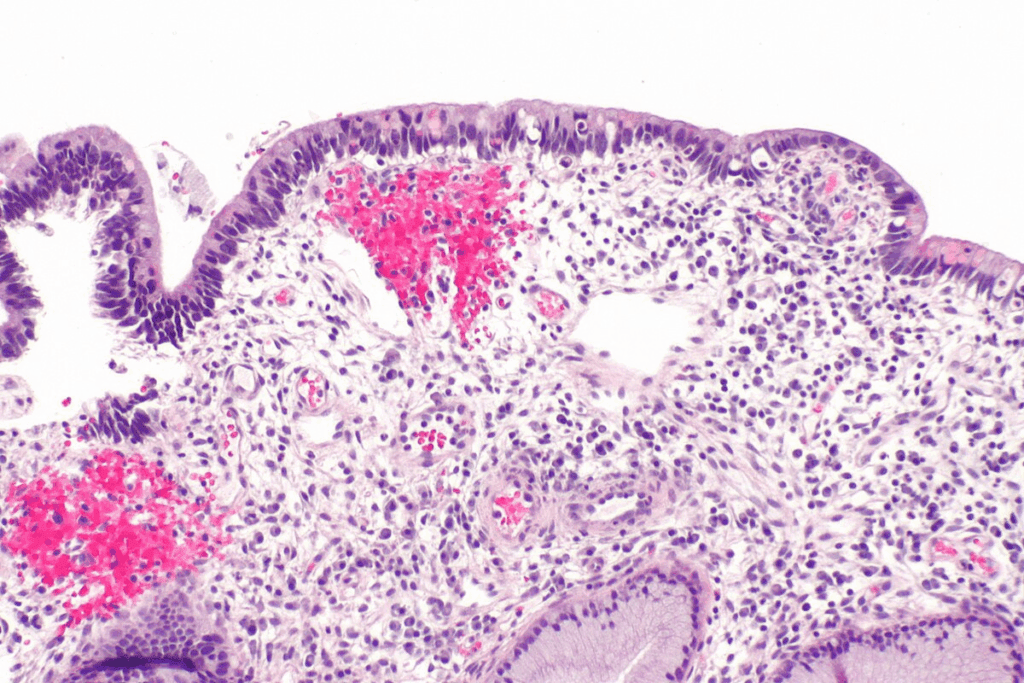

Carcinoma in situ has cancer cells that haven’t crossed the basement membrane. This membrane is a key barrier between cells and tissue. These cells look different from normal cells under a microscope.

Doctors diagnose carcinoma in situ by looking at these cell changes during a biopsy. These changes can range from mild to severe, showing how abnormal the cells are.

Looking at tissues under a microscope is the best way to diagnose CIS. It confirms CIS and tells it apart from invasive cancer.

It checks the cells and how they are arranged. Histological grading and molecular markers give more info on how likely the cancer is to grow.